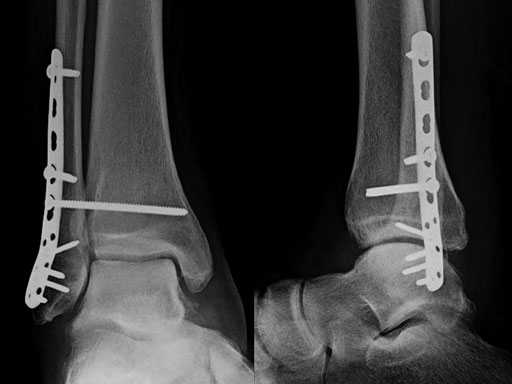

The LCP posterolateral distal fibula plate offers six round locking holes and two coaxial holes distally which accept 2.4 and 2.7 mm locking and cortex screws to provide multiple screw options. The distal holes are slightly divergent to help prevent screw pullout. The coaxial hole accepts both locking and cortex screws and its recess for screw heads minimizes screw-head prominence by allowing the screws to sit more flush with the plate, creating a low-profile construct. Its posterolateral position allows it to be placed deep to the peroneal muscles, minimizing the risk of wound healing problems due to prominence. A 2.7 mm lag screw may be placed through the distal screw cluster, and a syndesmotic screw may also be placed through the plate.

The anatomically precontoured plate shaft is only 2.25 mm thick yet substantially stronger than the one-third tubular plate. The combination holes in the shaft accept 3.5 mm locking screws, 3.5 mm cortex screws, and 4.0 mm cancellous bone screws.

The plate comes in left and right versions and is available in lengths from 77233 mm (3, 4, 5, 6, 7, 9, 11, 13, and 15 holes). It is offered in stainless steel and titanium, sterile, and nonsterile.